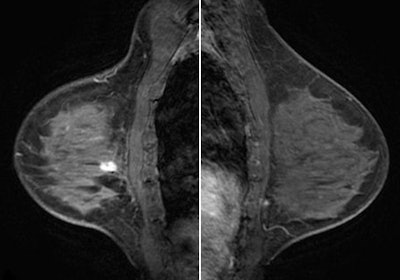

| Same view on MRI. |

When CEDM was compared to MRI for sensitivity of lesion detection, of all known sites of cancer in the breasts, CEDM found 30 of 33 (91%) and MRI found 32 of 33 (97%).

There were two false-negative index lesions, one for each technique. CEDM missed a heterogeneously dense, 21-mm infiltrating lobular carcinoma, and MRI missed a moderate parenchymal enhancing 7-mm infiltrating ductal carcinoma, Jochelson said. MRI also had three false positives compared to CEDM's zero.

As for specificity of the two technologies, of all enhancing lesions, CEDM identified 30 of 30 (100%) and MRI identified 30 of 37 (81%). (MRI found an additional seven lesions in the ipsilateral breast, while CEDM found an additional five.)